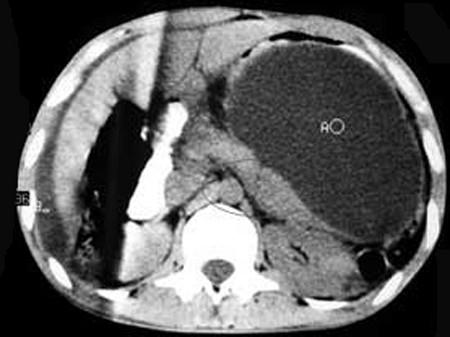

问题 男,33岁,腹部外伤后两月余,腹部疼痛,行CT扫描所见如图,最可能的诊断是 ( )

选项 A.急性胰腺炎 B.慢性胰腺炎 C.胰腺创伤性假性囊肿 D.畸胎瘤 E.腹腔包裹性积血

答案 C